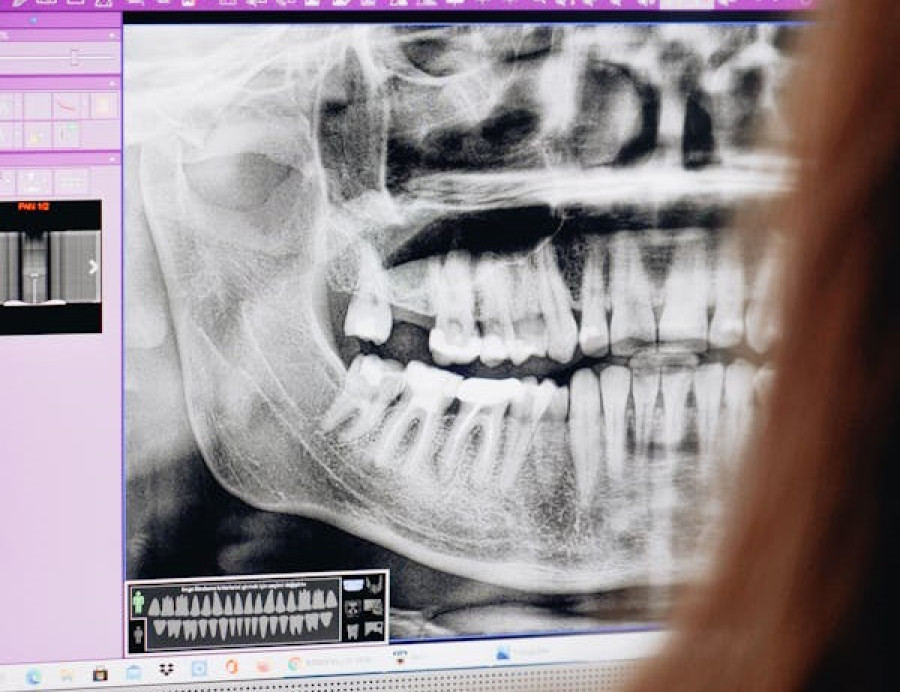

Сделайте рентген для определения точного расположения сверхкомплектного зуба.